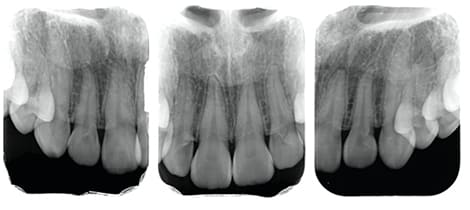

STEP 1

- 術前診査診断

手術前の状態の記録を取ります。

- 手術内容以外の処置に関してのレントゲン撮影並びに治療は別途保険内での費用が発生致します。